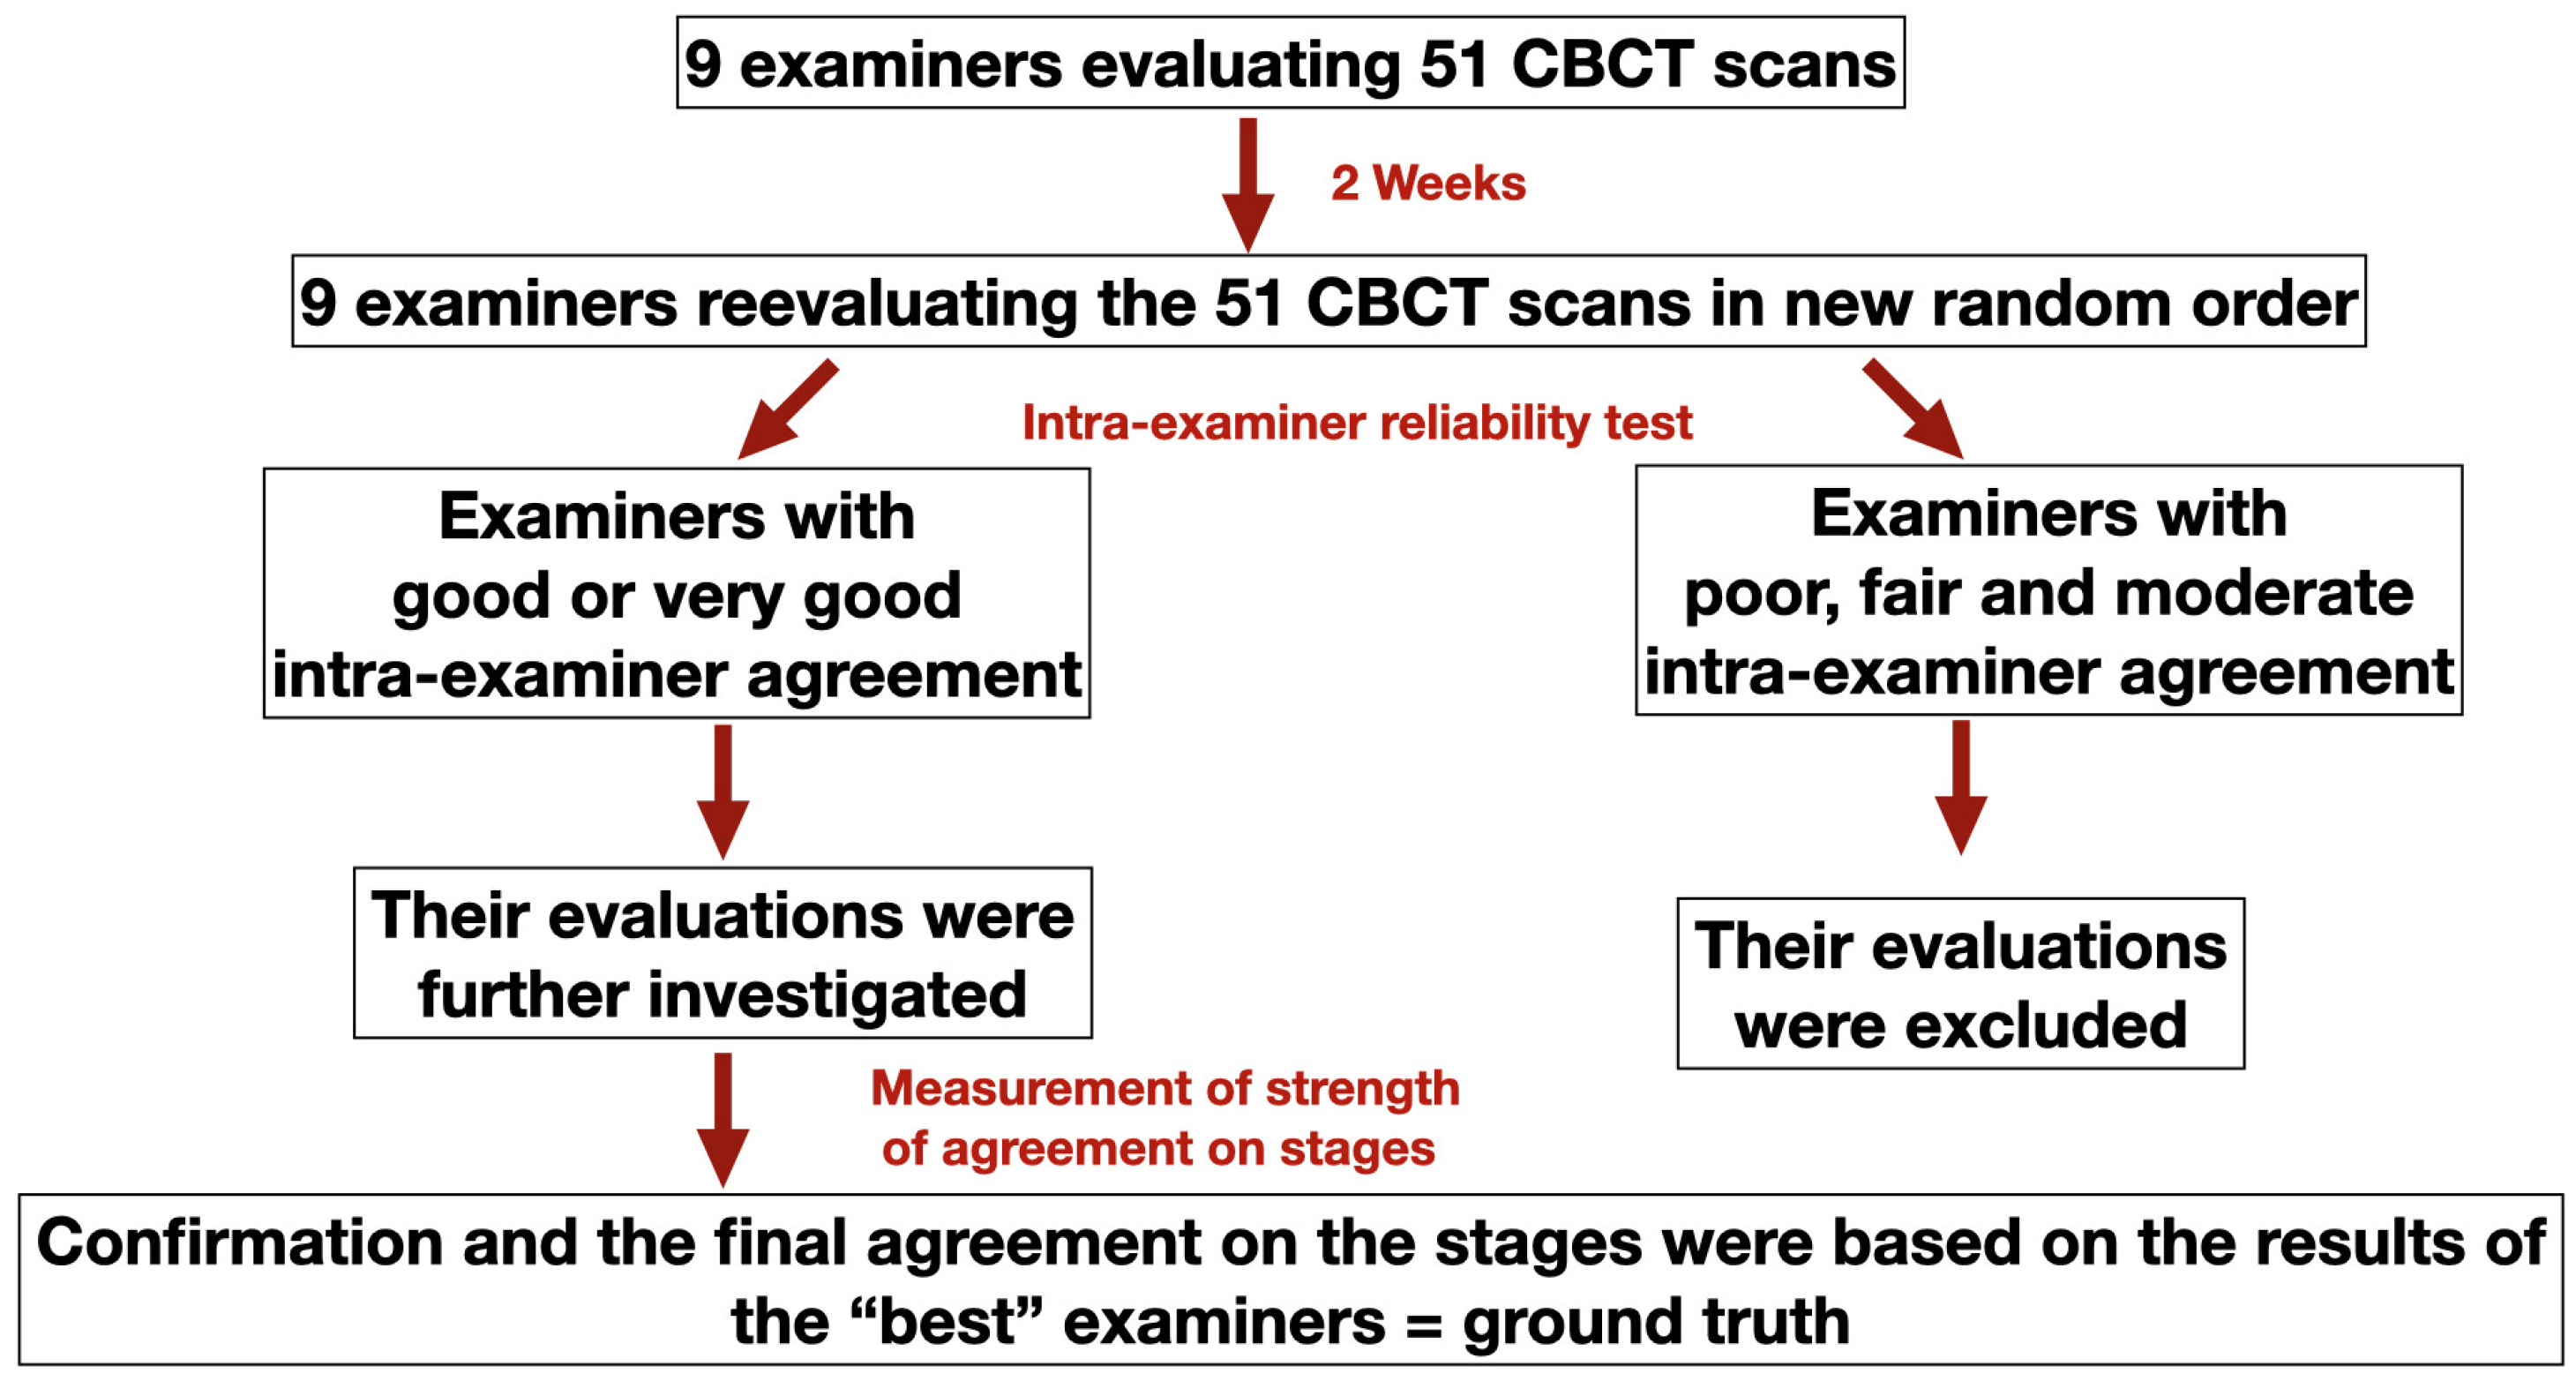

2. Materials and Methods

2.3. Assessment of MPS Maturation Stages According to Angelieri’s Classification Method

2.4. Statistical Analysis

3.1. Intra- and Inter-Examiner Reliability of MPS Maturation